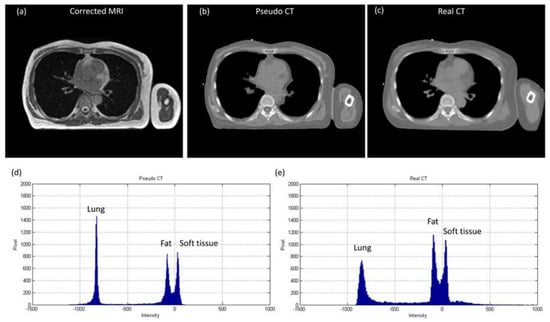

3.1. Chest Imaging for Cancer Treatment